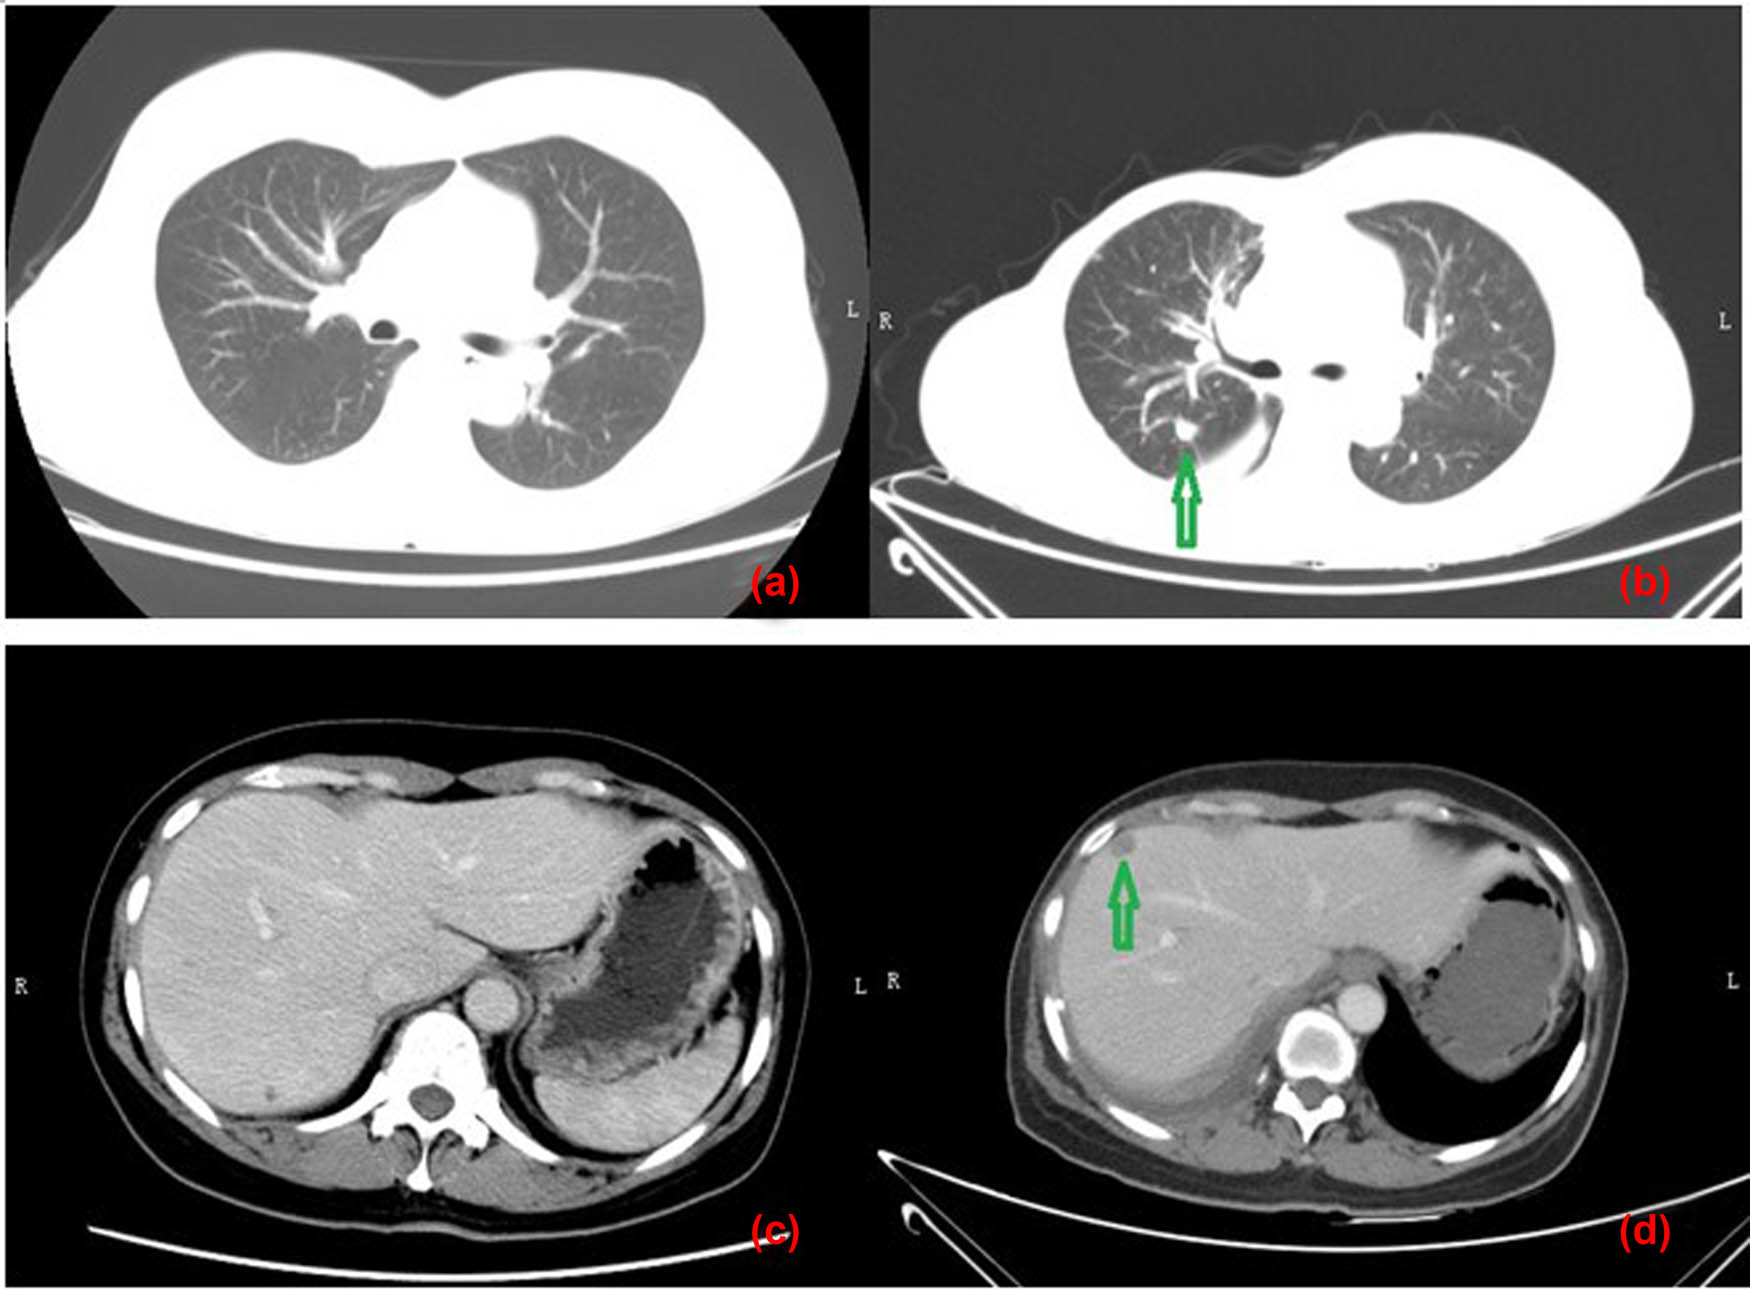

The patient underwent the breast mass excision surgery at that hospital without any further examinations and histopathologically (Figure 2) diagnosed with MBC with osseous differentiation, because there were two different components in the tumor; one was typical invasive ductal carcinoma (IDC) and the other was presenting as osteosarcoma with lots of immature trabeculae, and atypia osteocytes among them; there was no spindle cell component. Immunohistochemical analysis revealed that cells were CD10, CK-P and vimentin positive, estrogen receptor (ER), progesterone receptor (PR), human epidermal growth factor receptor 2 (HER-2), CD34, GATA-3, HMB45, smooth muscle actin (SMA), and p63 negative; proliferative index with KI-67 was 50%. Four days later, she was admitted to our hospital for further treatment. Chest computed tomography (CT) (Figure 3) indicated that there was no metastasis in the lung and liver; emission computed tomography (ECT) findings also revealed no signs of bone metastasis. Considering that the breast mass was a high-grade malignancy, and there was a suspected metastatic lymph node at the right axillary region; doctors suggested a biopsy of the lymph node under the guidance of US. However, the patient and her families refused and requested an excision of the sentinel lymph node. Histological results showed the lymph node metastasized from breast invasive carcinoma. Immunohistochemical analysis revealed that CK5/6 and p63 were positive. Subsequently, a modified radical mastectomy was performed, and there were no other metastatic lymph nodes (0/21). Finally, she was diagnosed with MBC with osseous differentiation, staged as TxN1M0.

Comparing CT plans of the lung and liver before the modified radical mastectomy and 24 months after the surgery. Images (a) and (c) were CT plans of the lung and liver before the modified radical mastectomy, respectively, and revealed no metastases. Images (b) and (d) were the corresponding plans 24 months after the surgery, and metastases were indicated by the green arrows.

The patient had received six cycles of TEC chemotherapy (docetaxel, 700 mg; epirubicin, 100 mg; cyclophosphamide 500 mg; 21 days), initiated after the modified radical mastectomy, and radiotherapy (RT) at a dosage of 48 Gy/25 f/5 days a week to treat the lymph node of the right superior and inferior clavicular fossa and right chest for 5 weeks. The follow-up investigations were advised every 6 months including breast, abdomen and lymph node US, blood routine, liver and kidney function, and tumor markers and chest CT every year. However, she did not perform any checking items for 18 months since RT. Twenty-four months later after surgery, she was admitted again for dyspnea and chest discomfort; chest CT (Figure 3) revealed that there were probable metastatic lesions in lungs (maximum: 29 mm × 27 mm), liver (maximum: 12 mm × 10 mm), and mediastinal lymph nodes (maximum: 26 mm), with pleural effusion in the right thoracic cavity. The lung nodule was diagnosed as metastasis from breast invasive carcinoma by CT guided needle biopsy (Figure 4). Immunohistochemical analysis revealed that cells were ER, PR, PF-L1, SOX10, Napsin A, thyroid transcription factor-1, GCDFP-15 negative, HER-2 (2+) but in situ hybridization negative, CK-P and GATA-3 positive, proliferative index with KI-67 was 40%, and BRCA1 was local positive. The patient refused further treatment and died 3 months later. The related indicators of tests and examinations throughout the patient are presented in Table 1.